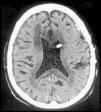

Spontaneous pneumocephalus following cerebrospinal fluid shunt is a rare complication. In most cases, the air enters in the intracranial cavity via a skull base defect. We report 2 cases of delayed tension pneumocephalus, secondary to ventriculoperitoneal shunt, and review the etiopathogenesis, prevention and treatment of this condition.